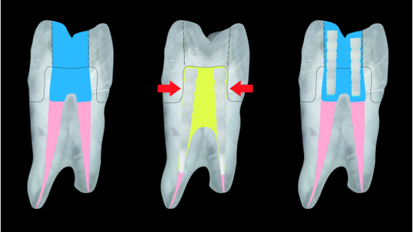

Historically, when a patient’s dental condition reached a state of total tooth loss, treatment was limited to a complete denture with no hope of ...